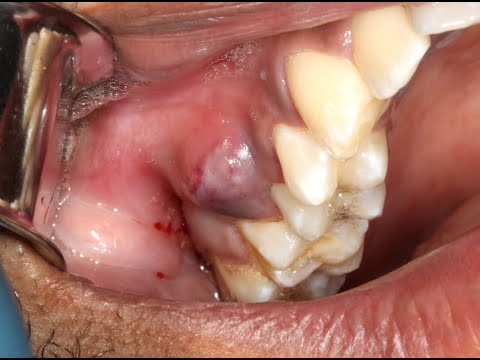

L’ascesso gengivale si sviluppa quando le gengive sono infiammate. Ciò può essere causato da una serie di fattori, tra cui l’accumulo di placca, la presenza di carie, l’uso di protesi dentarie e la mancanza di igiene orale. I principali sintomi dell’ascesso gengivale sono dolore intenso, gonfiore delle gengive, alitosi, difficoltà a masticare o parlare e presenza di una secrezione purulenta.

Se si notano i sintomi dell’ascesso gengivale, è importante rivolgersi immediatamente al dentista. Il trattamento può variare a seconda della gravità della situazione. In alcuni casi, può essere sufficiente una pulizia profonda del cavo orale, mentre in altri casi sarà necessario un intervento chirurgico.

Se l’ascesso gengivale scoppia da solo, si consiglia di rivolgersi subito al proprio dentista. Il medico potrà valutare la situazione e iniziare un trattamento adeguato. In alcuni casi, può essere sufficiente una semplice pulizia, mentre in altri casi sarà necessario un intervento chirurgico. È importante seguire attentamente le indicazioni del medico, in modo da evitare ulteriori complicazioni.